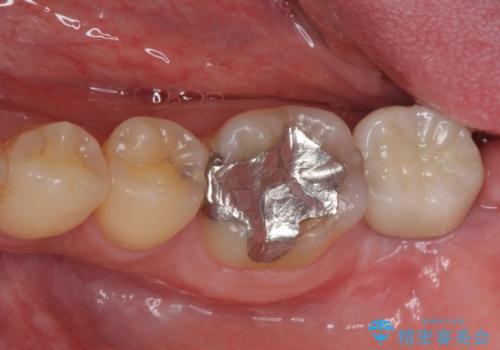

[20代男性] インプラント 失った歯の治療